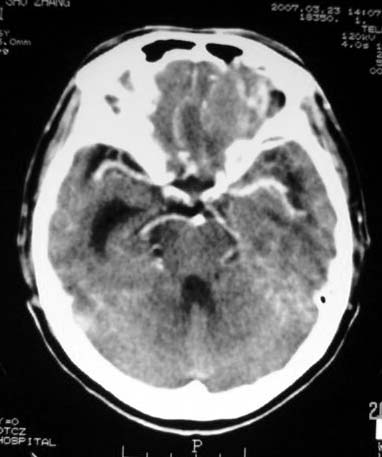

标题: CT7268:左额顶部病变增强片. [打印本页]

标题: CT7268:左额顶部病变增强片.

比较典型的少枝胶质细胞瘤ct表现,局部额骨垂直板有侵蚀变薄。

左额叶病灶内条片状高密度是钙化吗?是的话考虑少支胶质瘤可能大。不然有脑血畸形伴出血可能。

左侧额顶叶有条带状钙化的不规则形占位,增强呈不均匀轻度强化,局部颅骨受侵蚀变薄,典型的少支胶质细胞瘤。

比较典型的少枝胶质细胞瘤ct表现,局部额骨垂直板有侵蚀变薄